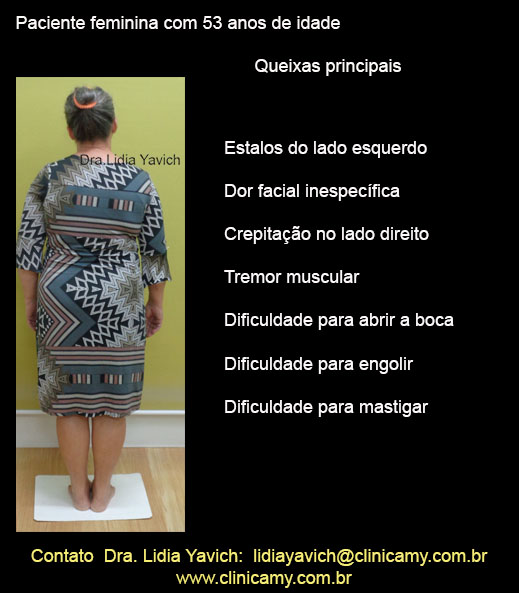

Paciente feminina com cinquenta e três anos de idade se apresenta a consulta com um histórico de distonia cervical. Refere movimentos involuntários.

Na ficha clinica registra também estalos na articulação temporomandibular ATM do lado esquerdo e crepitações na ATM do lado direito.

Relata ter tremores musculares e movimentos involuntários.

Dificuldade para abrir a boca, dificuldade para engolir e dificuldade para mastigar.